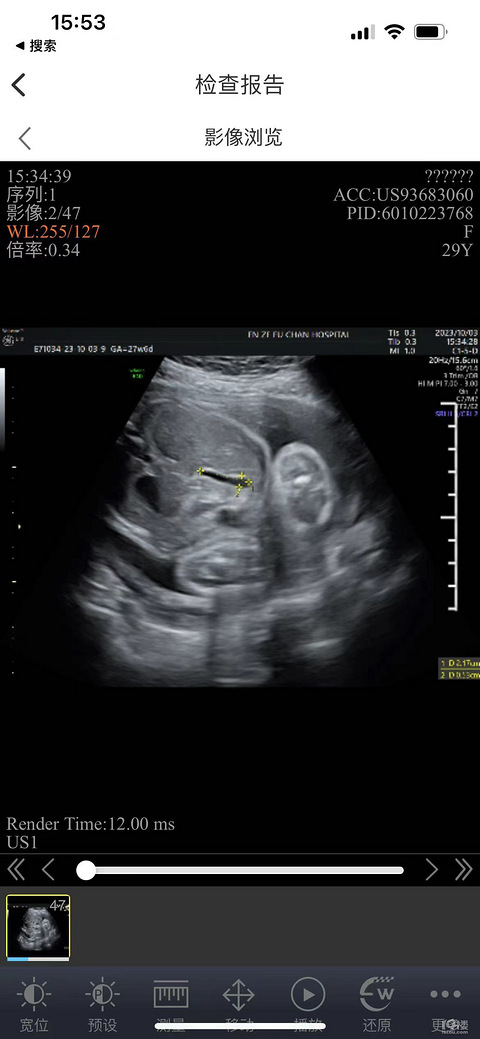

预产期:2024.4.29 建卡医院:台州市妇女儿童医院 产检医院:台州市妇女儿童医院 宝宝小名:奶茶 生产医院:准备妇儿 B超照片: 大排畸的时候查出来侧脑室偏宽,唉